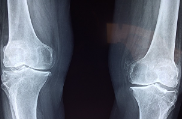

글루코사민은 관절 건강에 도움을 주는 물질 중 하나로, 연골 형성에 필요한 원료입니다. 관절염, 슬관절염, 퇴행성 관절염 등의 질환에서 연골이 파괴되고 손상될 때, 연골을 재생하고 유지하는 데 필요한 물질입니다. 또한, 운동 선수들이 부상 예방과 재활에 사용하는 것으로도 유명합니다. 일반적으로 글루코사민은 콘드로이친과 함께 복용하면 좋습니다. 글루코사민은 식품으로 섭취되거나, 보충제 형태로 복용할 수 있습니다. 하지만, 글루코사민은 약물과 함께 복용시 상호작용이 발생할 수 있으므로 주의가 필요합니다.

1. 연골 건강 개선: 글루코사민은 연골 조직을 구성하는 당질과 단백질의 생산을 촉진하여 연골 조직의 건강을 유지하는 데 도움이 됩니다. 연구에 따르면 글루코사민은 관절염 환자의 연골 손상을 예방하고 연골 조직 재생을 촉진할 수 있다는 것이 입증되어 있습니다.

2. 관절 염증 완화: 글루코사민은 관절 내부의 염증을 완화하는 데 도움이 됩니다. 이는 관절 통증과 관절 가동 범위 제한을 완화시키는 데 도움을 줄 수 있습니다.